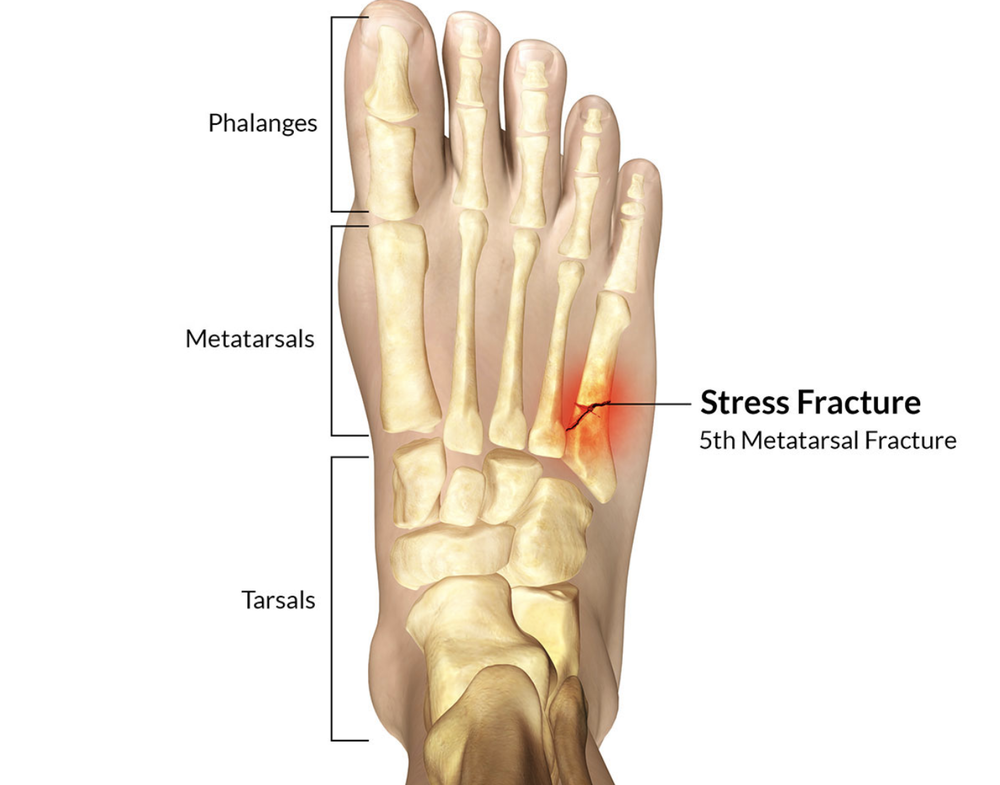

Diseases & conditions stress fractures of the foot and ankle a stress fracture is a small crack in a bone, or severe bruising within a bone. Introduction stress fractures refer to fractures occurring in the bone due to a mismatch of bone strength and chronic mechanical stress placed upon the bone. If left untreated, a stress reaction can eventually crack,.

Point tenderness, swelling and changes in your. Bottom line a stress fracture of the foot is a tiny crack in one of the bones in your foot. Stress fractures are tiny cracks in a bone.